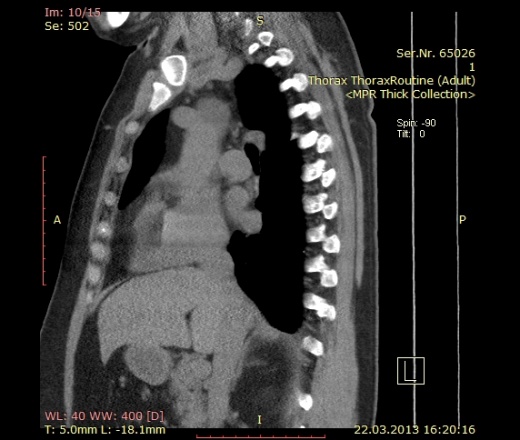

Пациентка 52 года. Поступила с жалобами на редкий сухой кашель, общую слабость, потливость, ощущение "лопания" в трахее, эпизодическое удушье. В ноябре 2012 перенесла двустороннюю полисегментарную пневмонию. Сейчас с подозрением на повторную пневомнию прислали на кт. В легких ничего особенного, а вот аорта меня заинтересовала.

Помогите с диф диагнозом. Думаю на расслоение аневризмы, но плотность этой штуки всего до 10 HU. Контрастирование не делаем, болюса нет((.

Пациентка 52 года. Поступила с жалобами на редкий сухой кашель, общую слабость, потливость, ощущение "лопания" в трахее, эпизодическое удушье. В ноябре 2012 перенесла двустороннюю полисегментарную пневмонию. Сейчас с подозрением на повторную пневомнию прислали на кт. В легких ничего особенного, а вот аорта меня заинтересовала.

Помогите с диф диагнозом. Думаю на расслоение аневризмы, но плотность этой штуки всего до 10 HU. Контрастирвоание не делаем, болюса нет((.

закачала архивом. легочное и средостенное окно. по 5 мм.

Ну, оценка аорты без контрастирования - это очень круто, но я бы отметил вероятность тромбированной аневризмы.

Сделали узи. Никакого намека на аневризму. Видимо киста такая.

без контраста по первому же кадру ясно, что это целомическая киста перикарда, классическое расположение и форма.